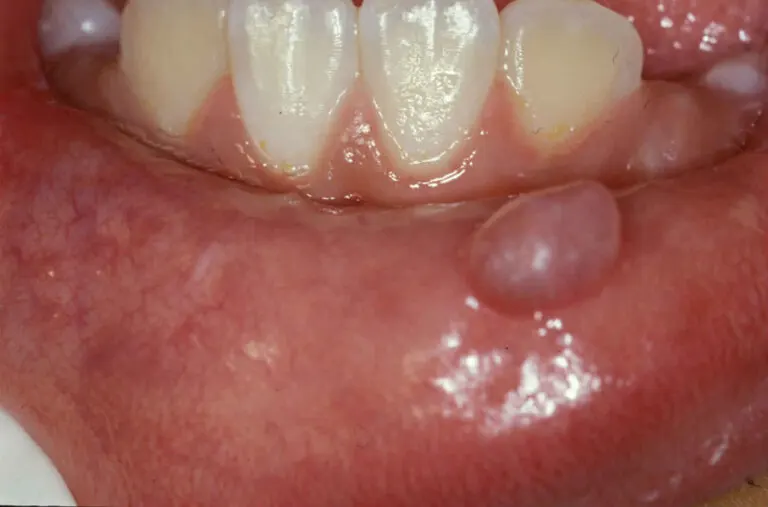

El mucocele o quiste mucoso oral es una causa frecuente de molestias en la boca al hablar o ingerir alimentos. Se presenta como un bulto o saco en los labios, la lengua, el paladar o las mejillas. ¿Te interesa conocer más? A continuación te contamos.

El mucocele se manifiesta de forma súbita como una pequeña ampolla o nódulo lleno de moco en el interior de la boca, en general en el labio inferior. Puede ser de coloración azul translúcida o mantener el mismo tono de la mucosa subyacente. Son indoloros, a menos que se acompañen de una herida.

Algunas personas suelen confundirlos con aftas bucales, no obstante, estas últimas son lesiones ulcerosas de bordes rojizos y centro blanco que generan dolor e incomodidad. A pesar de que el labio inferior es la localización más frecuente, también pueden formarse en la lengua, el paladar, la mucosa del carrillo y el piso de la boca.